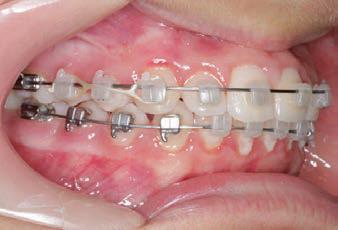

Carriere Motion 3D Appliance

Fastrack your orthodontic treatments. Save 6 months or more.

The SAGITTAL FIRST™ Philosophy is a time-tested approach that standardises, simplifies, and shortens Class II and Class III treatment times. It employs the Carriere Motion 3D Appliance to treat the AP dimension at the beginning of treatment before placing brackets or aligners. By resolving the most difficult part of treatment first, you can achieve a Class I platform in 3 to 6 months, shortening total treatment time by a minimum of 6 months1. You know how excited patients and parents become when you mention shorter treatment times.

CLASS II DIV.1 - Marra

PROVIDED BY: DR. LUIS CARRIÈRE

INITIAL - 4/4/18

PROGRESS 1 - 26/9/18 - Class I platform accomplished in 5.75 months with Motion 3D COLOR Appliance

PROGRESS 2 - 26/9/18 - Placement of the SLX 3D Clear Brackets

[CONTINUED ON NEXT PAGE]

with M-ONE .015 Cu Nitanium 27°

PROVIDED BY: DR. LUIS

PROGRESS 3 - 30/10/18 - With M-TWO .020 x .020 Cu Nitanium 35° archwire

PROGRESS 4 - 27/11/18 - 3 links power chain: 5, 4, bypass 3 to crimp hooks

PROGRESS 5 - 13/3/19 - With M-TWO .020 x .020 Cu Nitanium 35° archwire

PROGRESS 6 - 1/8/19 - With M-THREE.019 x .025 Beta Titanium wire

52 HENRY SCHEIN ORTHODONTICS

FINAL - 10/10/19 - Appliances removed AFTER

PROGRESS 7 - 10/10/19 - Final day in SLX 3D Clear Brackets BEFORE